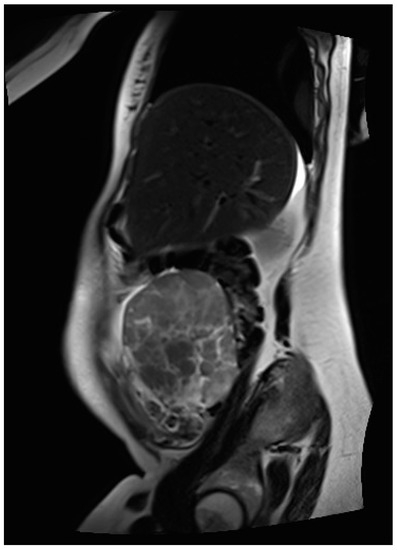

Thus, magnetic resonance imaging (MRI) was performed for further diagnostic clarification. Fetal MRI confirmed the pre-determined finding of the ultrasound, and the abdominal MRI showed an inhomogeneous formation, measuring 70 × 130 × 63 mm and located between the liver and uterus, as depicted in Figure 2. In addition, several individual, questionably communicating structures in a total extent of about 58 × 29 × 71 mm diameter of analogous morphology could be detected in the left lower abdomen, some of which could not be well distinguished from the adjacent intestine. The structures primarily emanated from the adnexa. Furthermore, moderate ascites, especially in the pelvis minor with questionable, small, nodular changes in the cavum Douglasi were visible. At this point, there were three differential diagnoses: granulosa cell tumors, decidualized endometriomas, and malignant neoplasia.

Figure 2.

MR image of the inhomogeneous, mainly solid tumor located in the right middle abdomen, primarily deriving from the right adnexa.